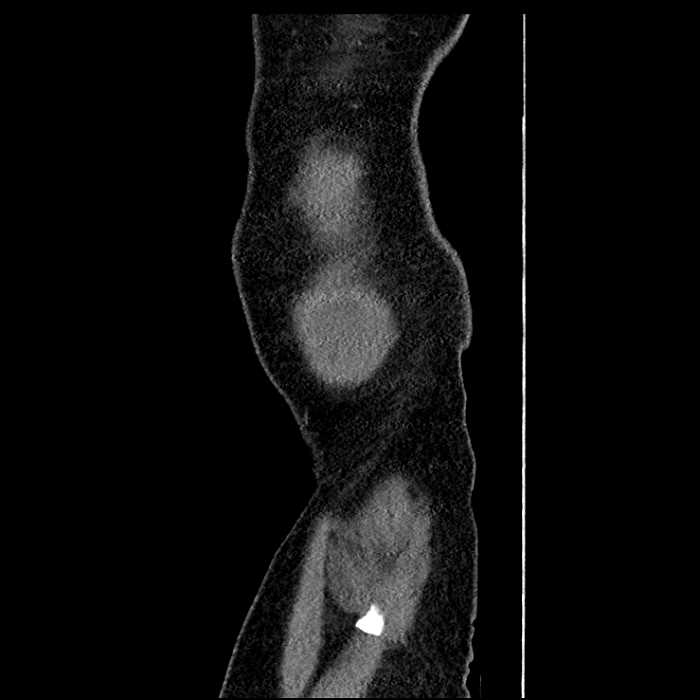

• Mild mural thickening of a segment of the sigmoid colon with adjacent fat stranding and a 1.5 cm fluid and gas collection along the tip of an inflamed diverticulum

• Loss of the normal fat plane between this collection and adjacent loops of small bowel, which demonstrate mural thickening

Acute sigmoid diverticulitis complicated by a small contained perforation and a large abscess in the right hepatic lobe. Additional small subcapsular abscesses along the anterior margin of the left hepatic lobe.

Additionally, loss of the normal fat plane between the peridiverticular collection and adjacent thickened loops of small bowel raises the potential for an enterocolonic fistula.

Hepatic abscess showing the double target sign with low density internally surrounded by a thin inner enhancing rim (red arrow) and ill-defined outer low density rim (yellow arrow). Blue arrow indicates an internal septation. Red arrows: additional smaller subcapsular abscesses. Red arrow: focal contained perforation associated with diverticulitis.